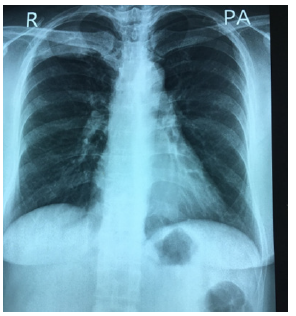

Urine examination was normal. LE cell was negative, Extractable nuclear antigen profile was negative. Serum creatinine and blood urea were normal. Ultrasound abdomen was normal. Chest radiograph showed an ill- defined mass, 3cm in largest diameter at right apical area with erosion of the 4th rib. It is shown in Figure 1. It became larger over 1year as demonstrated in Figure 2. CT scan chest revealed a mass at posteromedial site with the 4th rib erosion Figures 3,4. The other investigations were as follows: hemoglobin 12g%; total WBC count 6.2X109/L; platelets normal. Liver function tests were normal. Lung function test showed normal FEV1; normal FEV1 and FVC ratio. The cholesterol was raised. Her blood group was B Rh negative (Figure 1-4).